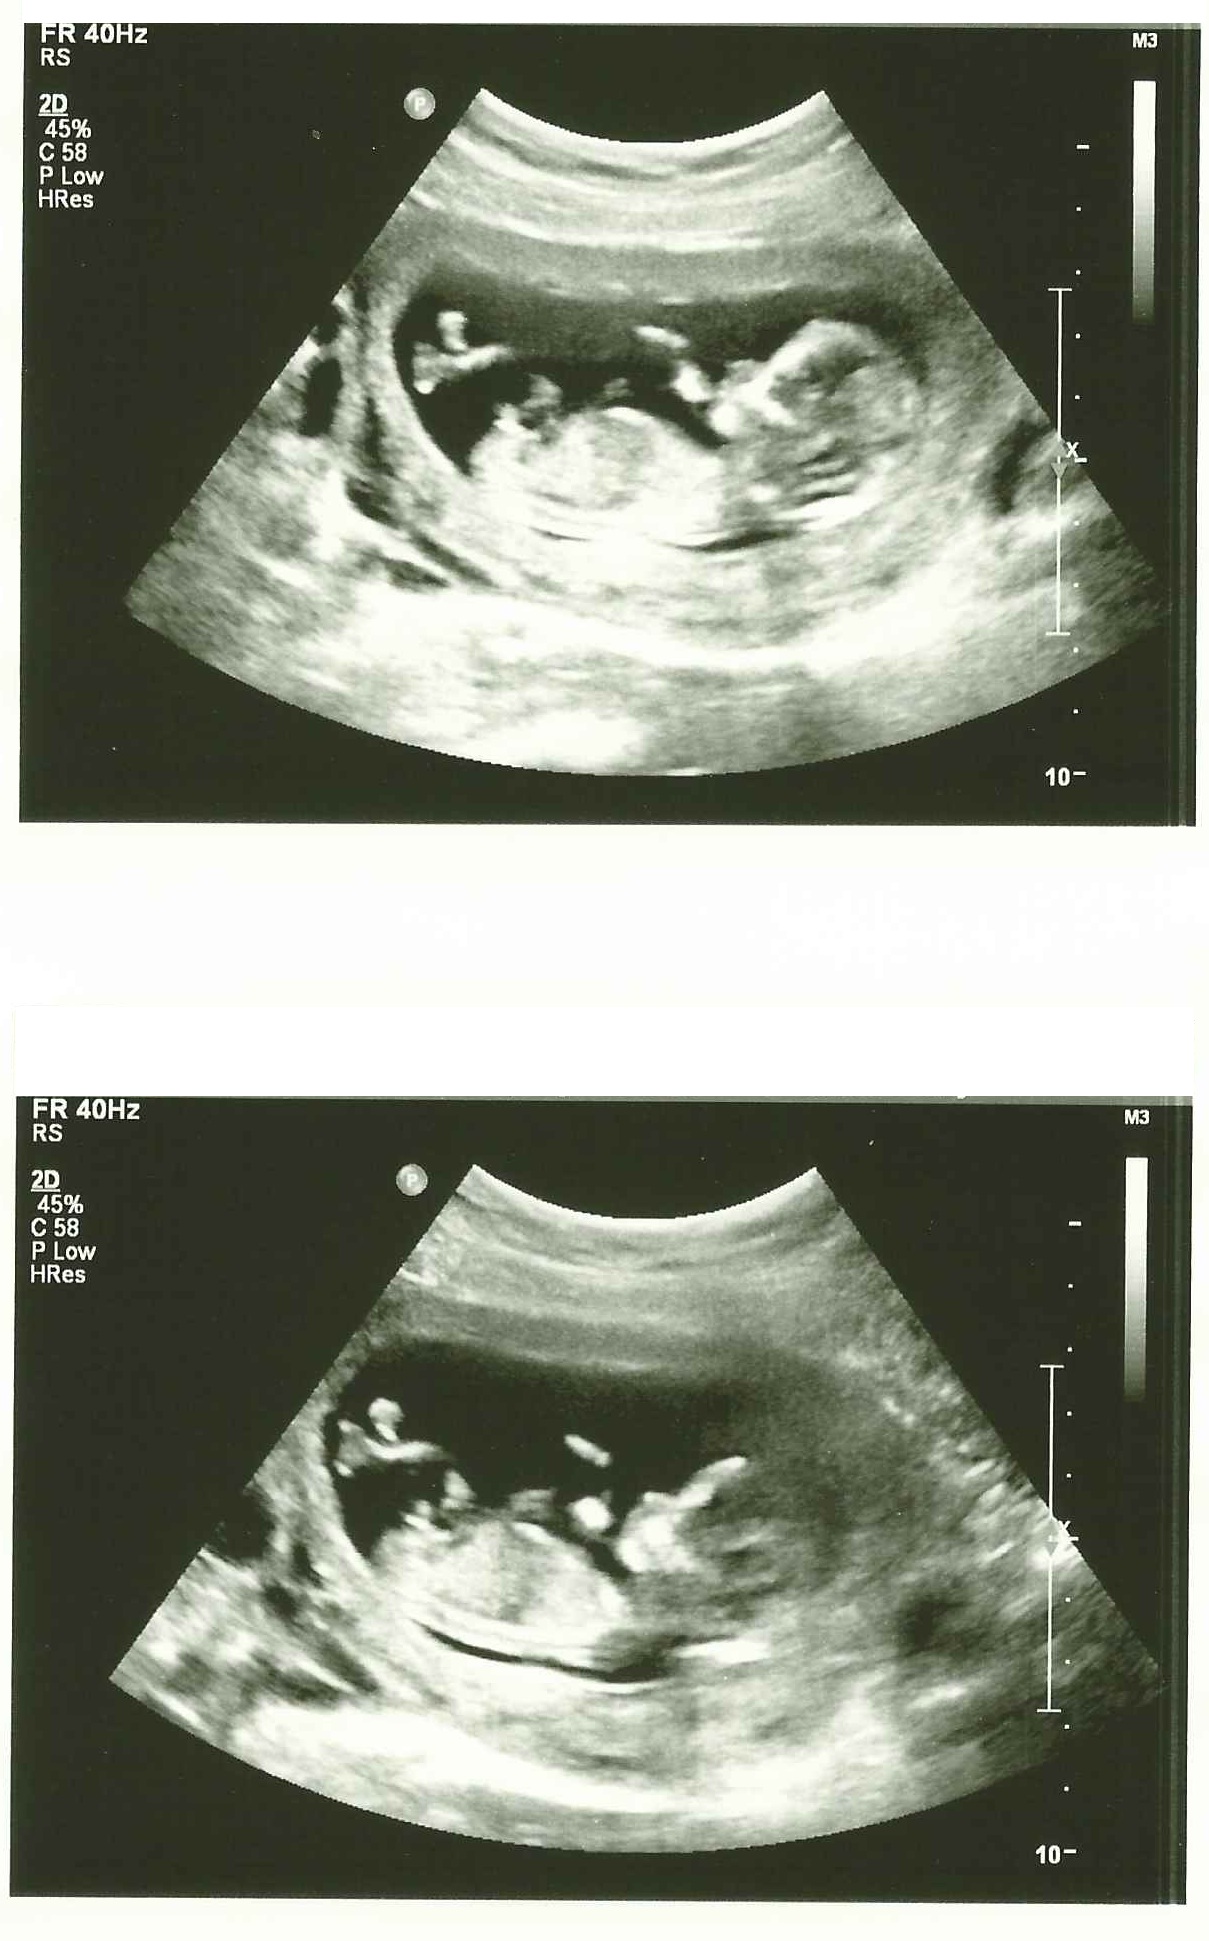

13 W NT scan....what do you guys think?